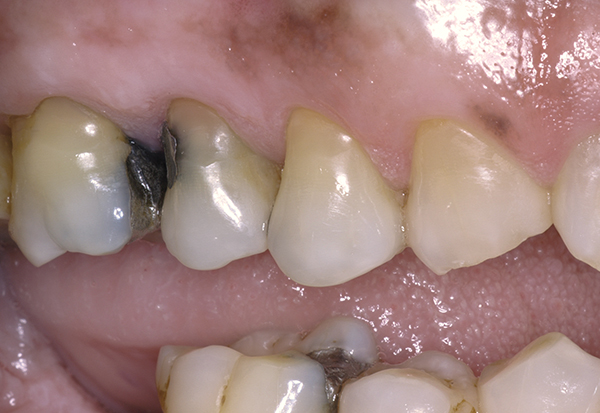

(Figure 4.) Gingival recession with exposed root surfaces are susceptible to dentinal hypersensitivity facial surfaces of maxillary teeth with recession with symptoms of dentin hypersensitivity.

Figure 4